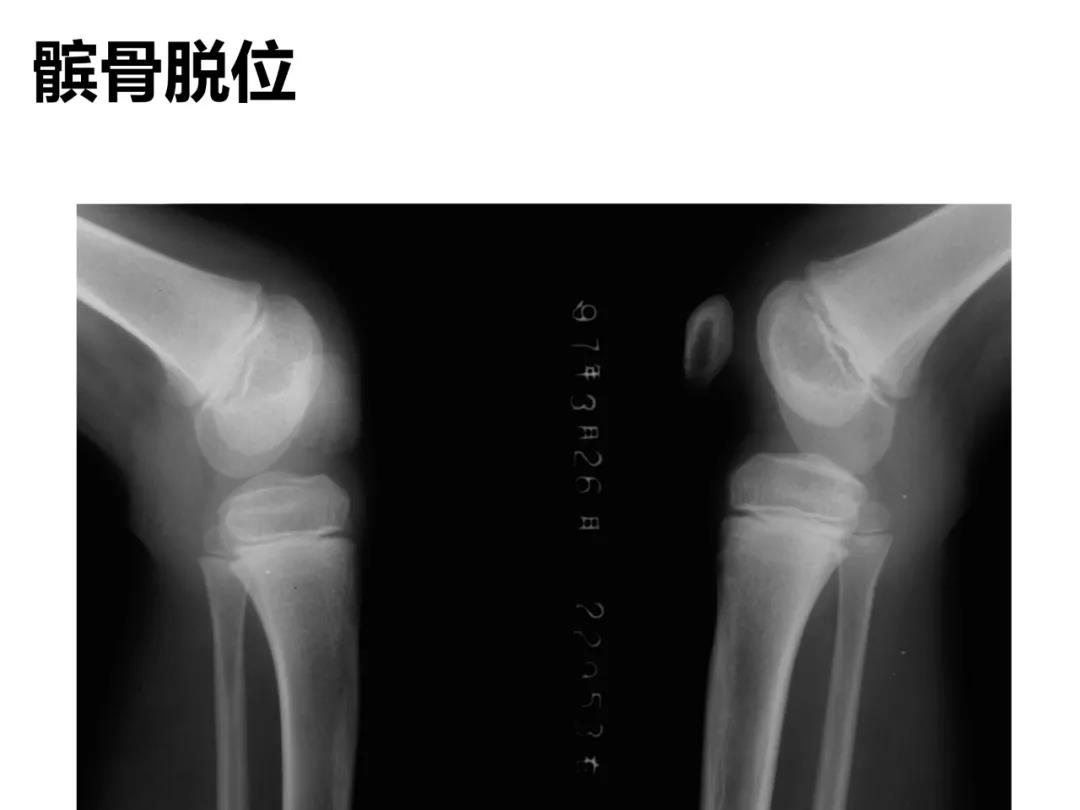

小儿骨科X线片汇总,临床读片宝典!